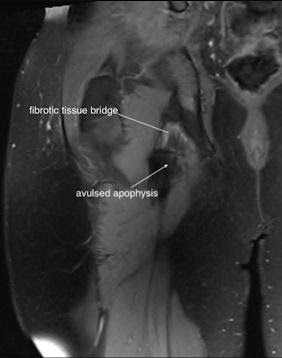

The mechanism of injury involved a sudden explosive sprint effort causing a massive avulsion of ischial tuberosity, including a part of the bony origin (see figures 12 and 13).

Figure 12

Figure 13 – MRI coronal right hip

This was treated as a hamstring tear for approximately a year. The young teenager subsequently developed disabling sitting pain interfering with studies as well as sciatic nerve irritation due to local compression. If this was identified early it could have been treated surgically.